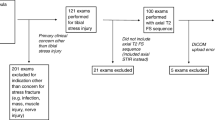

A musculoskeletal MRI database was used to identify 131 consecutive patients who were referred for an MRI examination of the lower extremity at our institution between 1 January 1998 and 1 March 2006 to rule out tibial stress injury. Eighty of these 131 patients had a radiographic examination of the tibia performed within 2 weeks of their MRI examination. The study group consisted of these 80 patients (21 males and 59 females; aged between 14 years and 44 years with an average age of 22 years) with suspected tibial stress injuries who were evaluated with radiographs and MRI. Nineteen patients complained of bilateral tibial pain and had imaging studies performed on both lower extremities. Thus, a total of 99 tibias were evaluated with radiographs and MRI.

Statistical analysis

The sensitivity with 95% confidence intervals of radiographs for detecting symptomatic tibial stress injuries was calculated using MRI as the gold standard. Sensitivity was defined as the proportion of individuals with MRI findings of tibial stress injury who had a concordant abnormality identified on radiographs.

T-tests were used to compare the duration of clinical symptoms in patients with and without a positive radiograph. A positive radiograph was defined as a radiograph that showed an abnormality that corresponded to the location of the patient’s clinical symptoms and MRI abnormalities. A difference in the duration of clinical symptoms in patients with and without a positive radiograph was considered to be statistically significant if the p value was less than 0.01.

Fisher’s exact tests were used to compare the proportion of patients with and without a positive radiograph who had various MRI findings indicating a severe tibial stress injury. These MRI findings included severe periosteal edema, periosteal edema more than 2 mm thick, severe bone marrow edema, bone marrow edema more than 5 cm in longitudinal length, intracortical signal abnormality, and a Fredericson grade 4 stress injury. A positive radiograph was defined as a radiograph that showed an abnormality that corresponded to the location of the patient’s clinical symptoms and MRI abnormalities. A difference in the proportion of patients with and without a positive radiograph who had the various MRI findings was considered to be statistically significant if the p value was less than 0.01. Fisher’s exact tests were also used to calculate odds ratios and 95% confidence intervals describing the relative risk of a patient with a positive radiograph having these MRI findings compared with a patient without a positive radiograph.

Statistical analysis

Radiographs had a sensitivity of 15% (13 out of 86 tibia; 95% confidence interval between 8% and 24%) for detecting tibial stress injury. There was no statistically significant difference (p = 0.91) in the duration of clinical symptoms in patients with and without a positive radiograph. In fact, patients with a positive radiograph had, on average, a shorter duration of clinical symptoms than patients without a positive radiograph. There was a statistically significantly higher (p < 0.01) proportion of patients with a positive radiograph than without a positive radiograph who had severe periosteal edema, periosteal edema more than 2 mm in thick, severe bone marrow edema, bone marrow edema more than 5 cm in longitudinal length, intracortical signal abnormality, and a Fredericson grade 4 stress injury. Table 4 shows the odds ratios and 95% confidence intervals describing the relative risk of a patient with a positive radiograph having various MRI findings indicating a severe tibial stress injury compared with a patient without a positive radiograph.